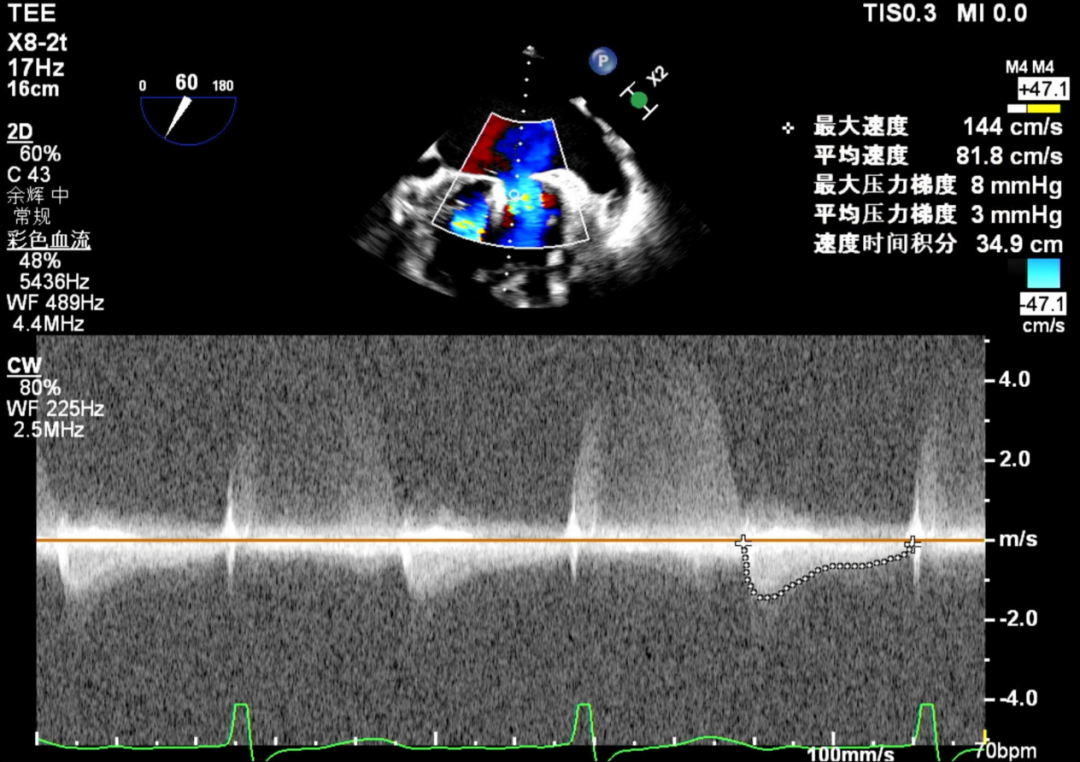

术前肺静脉频谱